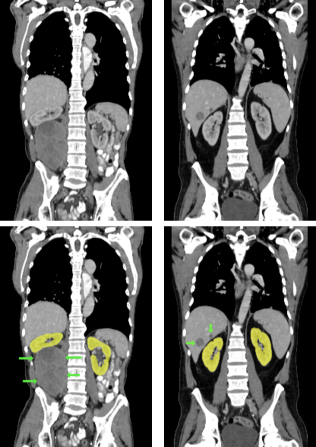

Figure 3: Four examples of CT scans from the training set (dataset A) showing coronal sections with annotations in format 2 (see Figure 2(c)) where yellow and red overlays represent annotations of the parenchyma and kidney abnormalities, respectively. Note that all the patients have anomalies in the body (green arrows in the body), and both cases of (b) have only one kidney and contain kidney abnormalities. All the slices have a window center of 60 HU and a window width of 360 HU.

Samples of CT scans from patients included in this study can be seen in Figure 3. While Figure 3(a) depicts patients without kidney abnormalities, it highlights the presence of abnormalities in other parts of the body, such as liver tumors. Figure 3(b) shows patients with kidney abnormalities, as well as other abnormalities in the body, such as nephrectomy and collapsed lung.